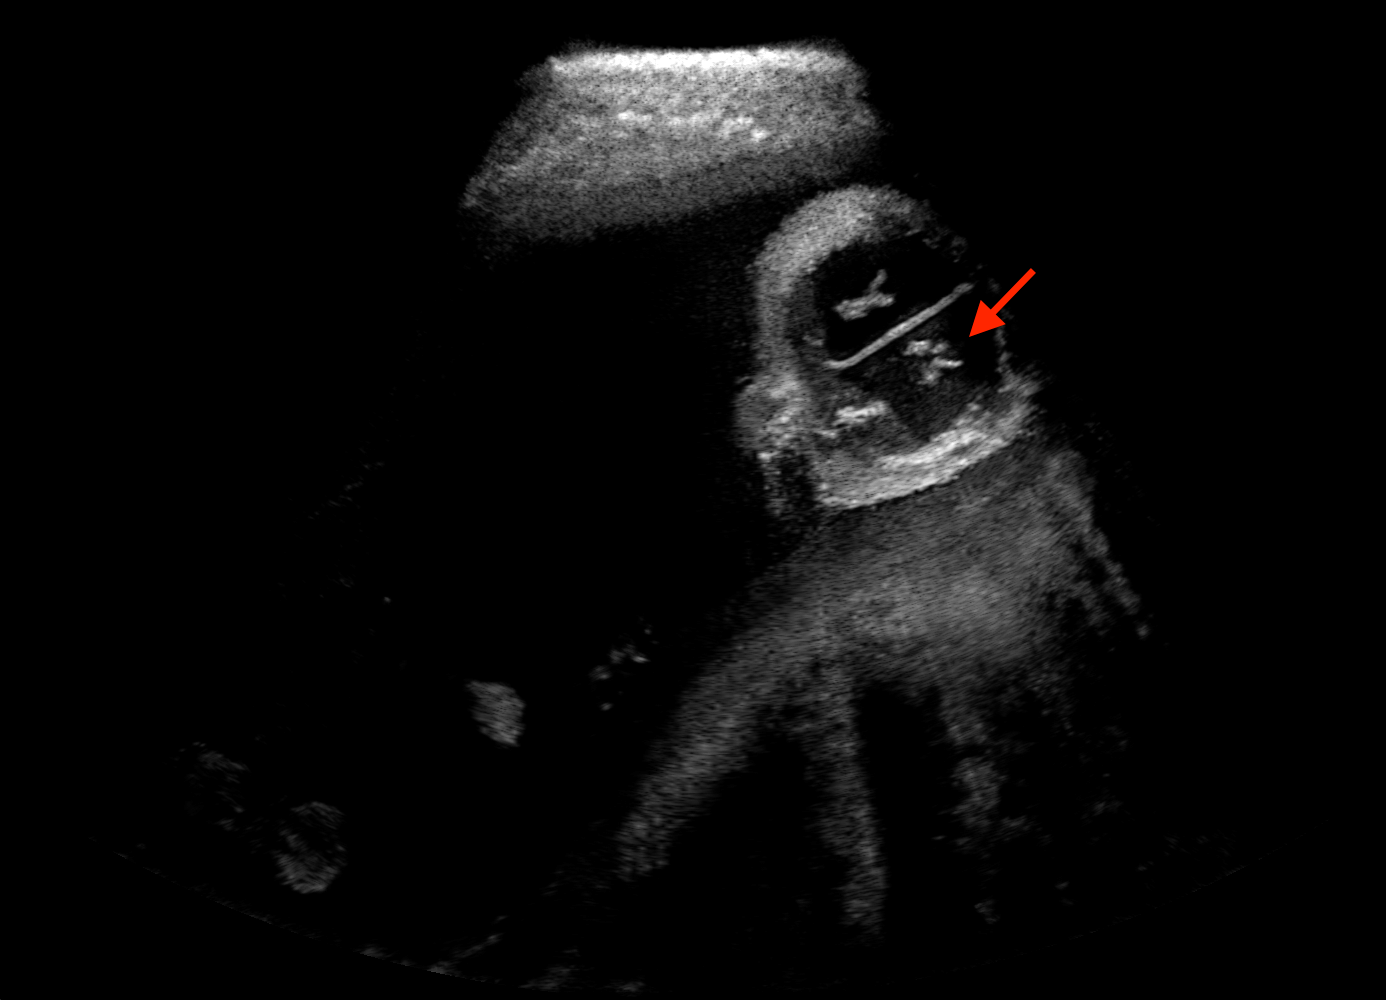

Qualitative evaluation.

Fig. 2 depicts the qualitative results for all the models mentioned above, with arrows pointing at structures relevant to discussion points below. The visual results of the ablated variants of SA2H show substantial quality degradation compared to the full SA2H model, demonstrating the importance of each proposed architectural contribution. Given only segmentation map in the network input, SA2H-att fails to generate acoustic shadows, e.g. those cast by the ribs. Detailed structures such as the cervical vertebrae are blurred out in the SA2H-concat results, which also contain hallucinated structures mainly due to insufficient preservation of input information along the encoding-decoding path. With SA2H-conv, checkerboard artefacts are observed due to the lack of proposed additional stride-1 convolutional layers. SA2H-noise without any explicit noise input is seen to be sub-optimal at generating textural details. The baseline method NSA2H fails to preserve anatomical structures and acoustic shadows in all cases, while the simulated textures also show significant artefacts such as checkerboard patterns. Realism of different simulation aspects may become relevant given different clinical applications and scenarios. For instance, improved structural preservation, e.g. with the hyperechoic bony structures such as the skull and the ribs, of the final model over its ablated variants and NSA2H may prove relevant in fetal head measurements, while the textural improvements facilitating screening fetal organ maturity, e.g. lungs. Compared to the silver-standard model LSA2H with a low-quality rendered image as additional input, SA2H is seen to be on par in structural preservation. Note that shadowing on homogenous regions (e.g. the rib shadowing on the homogenous lung region on the 4th column of Fig. 2) with our proposed method SA2H is represented more faithfully compared to LSA2H, whereas shadows on structurally complex regions (e.g. the skull shadowing around the heart and surrounding tissues on the 3rd column of Fig. 2) are suboptimal with our SA2H. Therefore, one may have to evaluate our method given particular simulation tasks, e.g. its clinical validity for fetal heart exams. However, even with low quality rendered images, LSA2H leads to artificial enhancements of intensities, lack of acoustic shadows, and low-quality textures especially near the probe, for which SA2H yields satisfactory results as illustrated in Fig. 2.

(a) Target

(b) SA2H

(c) SA2H-att

(d) SA2H-concat

(e) SA2H-conv

(f) SA2H-noise

(g) NSA2H

(h) LSA2H

For the interpretation of the local errors, sample spatial p error maps are depicted in Fig. 3 for LSA2H, NSA2H, and SA2H for the middle two examples shown in Fig. 2. Both images generated by NSA2H have a lot of missing structures and accordingly have high error almost all over the map. Artificial skull enhancement with LSA2H is seem to evoke large p error, as shown in the corresponding error map, whereas the bright spots in the error map of SA2H reflect some hallucinated shadows and structure in the brain. All of above mentioned regions of interest are marked by red arrows. In the bottom example, SA2H fails to generate faithful content at the bottom region marked by red circles, which is well indicated by the error map as well.